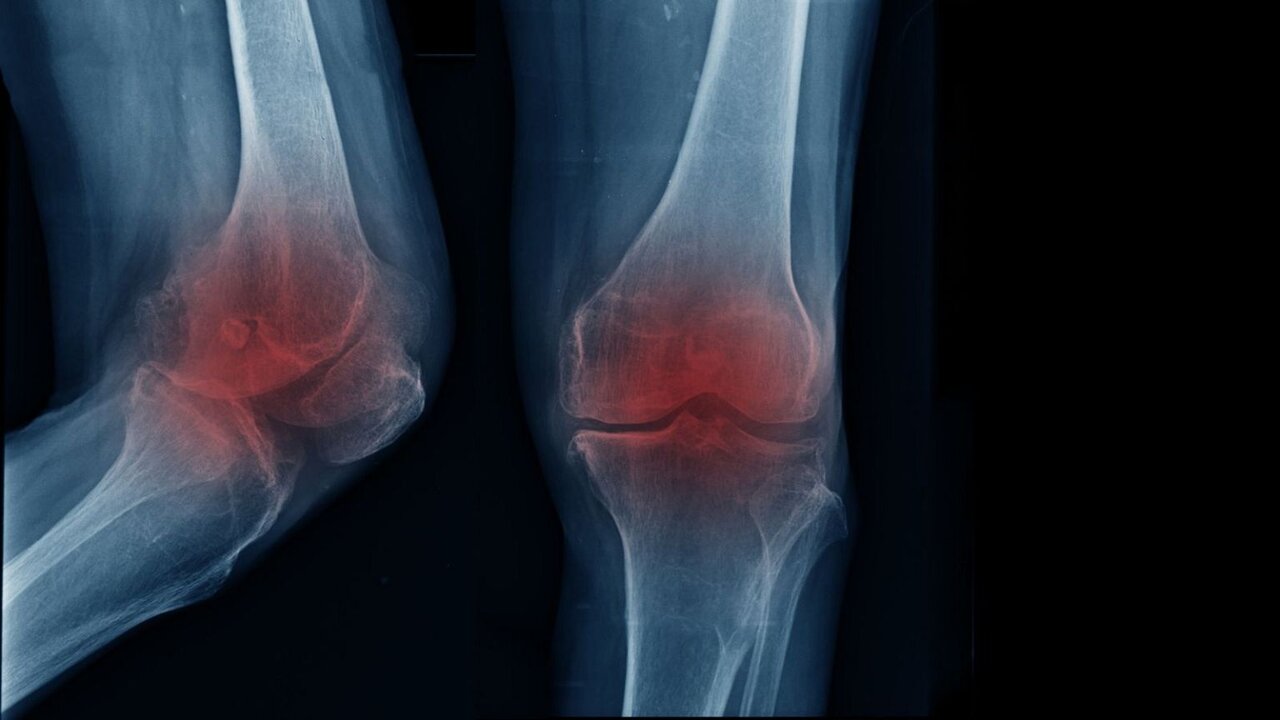

متخصص ارتوپدی و فلوشیپ جراحی زانو با بیان اینکه مفصل زانو یکی از فعالترین بخشهای بدن به شمار میرود و در طول زندگی فشار زیادی را تحمل میکند، تصریح کرد: با گذشت زمان و افزایش سن، لایه غضروفی این مفصل به تدریج نازک و فرسوده میشود و همین روند میتواند زمینهساز بروز آرتروز یا ساییدگی زانو باشد.

اکبری اقدم با بیان اینکه زمانی که این غضروف کارکرد طبیعی خود را از دست بدهد، حرکت مفصل با مشکل همراه و درد و محدودیت حرکتی ظاهر میشود، ادامه داد: بروز آرتروز زانو همیشه به یک عامل مشخص محدود نمیشود و دلایل گوناگونی در ایجاد آن نقش دارند.

متخصص ارتوپدی و فلوشیپ جراحی زانو با تاکید بر اینکه شایعترین علامت آرتروز زانو درد است که به طور معمول در مراحل ابتدایی هنگام راه رفتن یا فعالیت بروز میکند، اضافه کرد: با پیشرفت تخریب غضروف، شدت درد افزایش مییابد و ممکن است حتی در حالت نشسته یا استراحت نیز فرد را آزار دهد.

اکبری اقدم با بیان اینکه علاوه بر درد، احساس خشکی مفصل به ویژه پس از بیدار شدن از خواب، کاهش دامنه حرکتی و دشواری در انجام حرکات روزمره نیز از نشانههای رایج این بیماری محسوب میشود، افزود: اگرچه افزایش سن نقش مهمی در ابتلاء به آرتروز زانو دارد، اما سبک زندگی نیز تأثیر قابل توجهی در زمان بروز آن ایفا میکند.